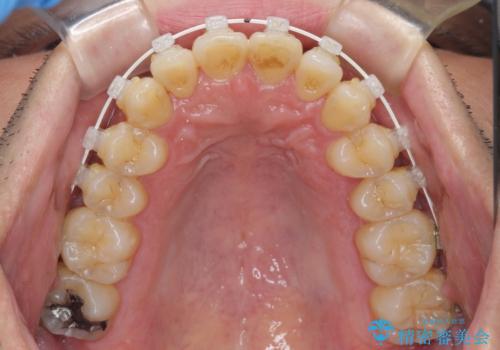

前歯のデコボコ ワイヤー装置での短期間治療

- 前歯のデコボコを気にして来院された患者様です。

インビザラインまたはワイヤー装置、どちらでも対応可能でしたが、自己管理の少なさ、期間の短さから、ワイヤー装置による矯正治療を行うこととしました。

治療開始の頃は、食事や歯磨きが慣れず、装置が頻繁に脱落しましたが、2,3ヶ月ほどで慣れ、その後は1年ほどで治療を終えることができました。